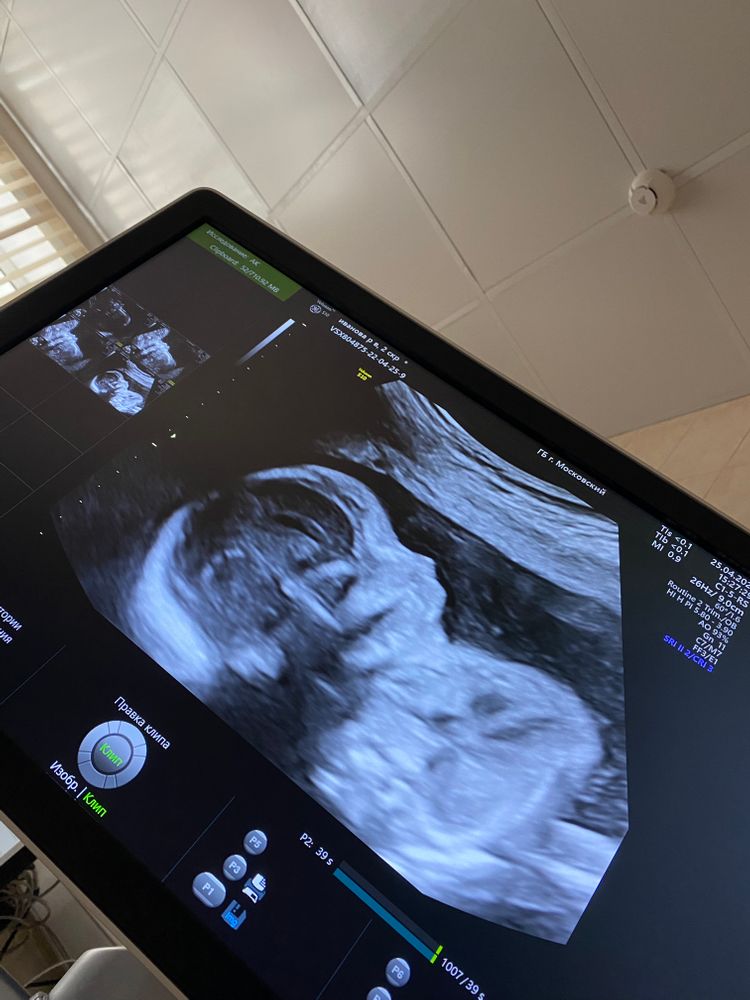

На память. Второй скрининг. Пол 🙈

Пошла наша 21 неделя, сегодня была на скрининге. В итоге у нас не мальчик, а девочка. Такие дела 😃💓

Развивается согласно сроку, все хорошо, слава Богу. Весим мы почти 400 грамм. Шейка 35 мм.

Активничает, пинается вовсю))) плацента наконец поднялась ,я очень переживала из-за этого